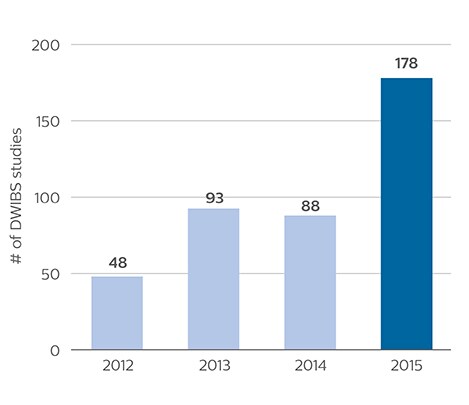

As oncologists and surgeons have learned more about DWIBS, referrals for the exams have increased. In 2015, the 326-bed hospital’s radiology department doubled their number of whole body DWIBS exams compared to 2014.